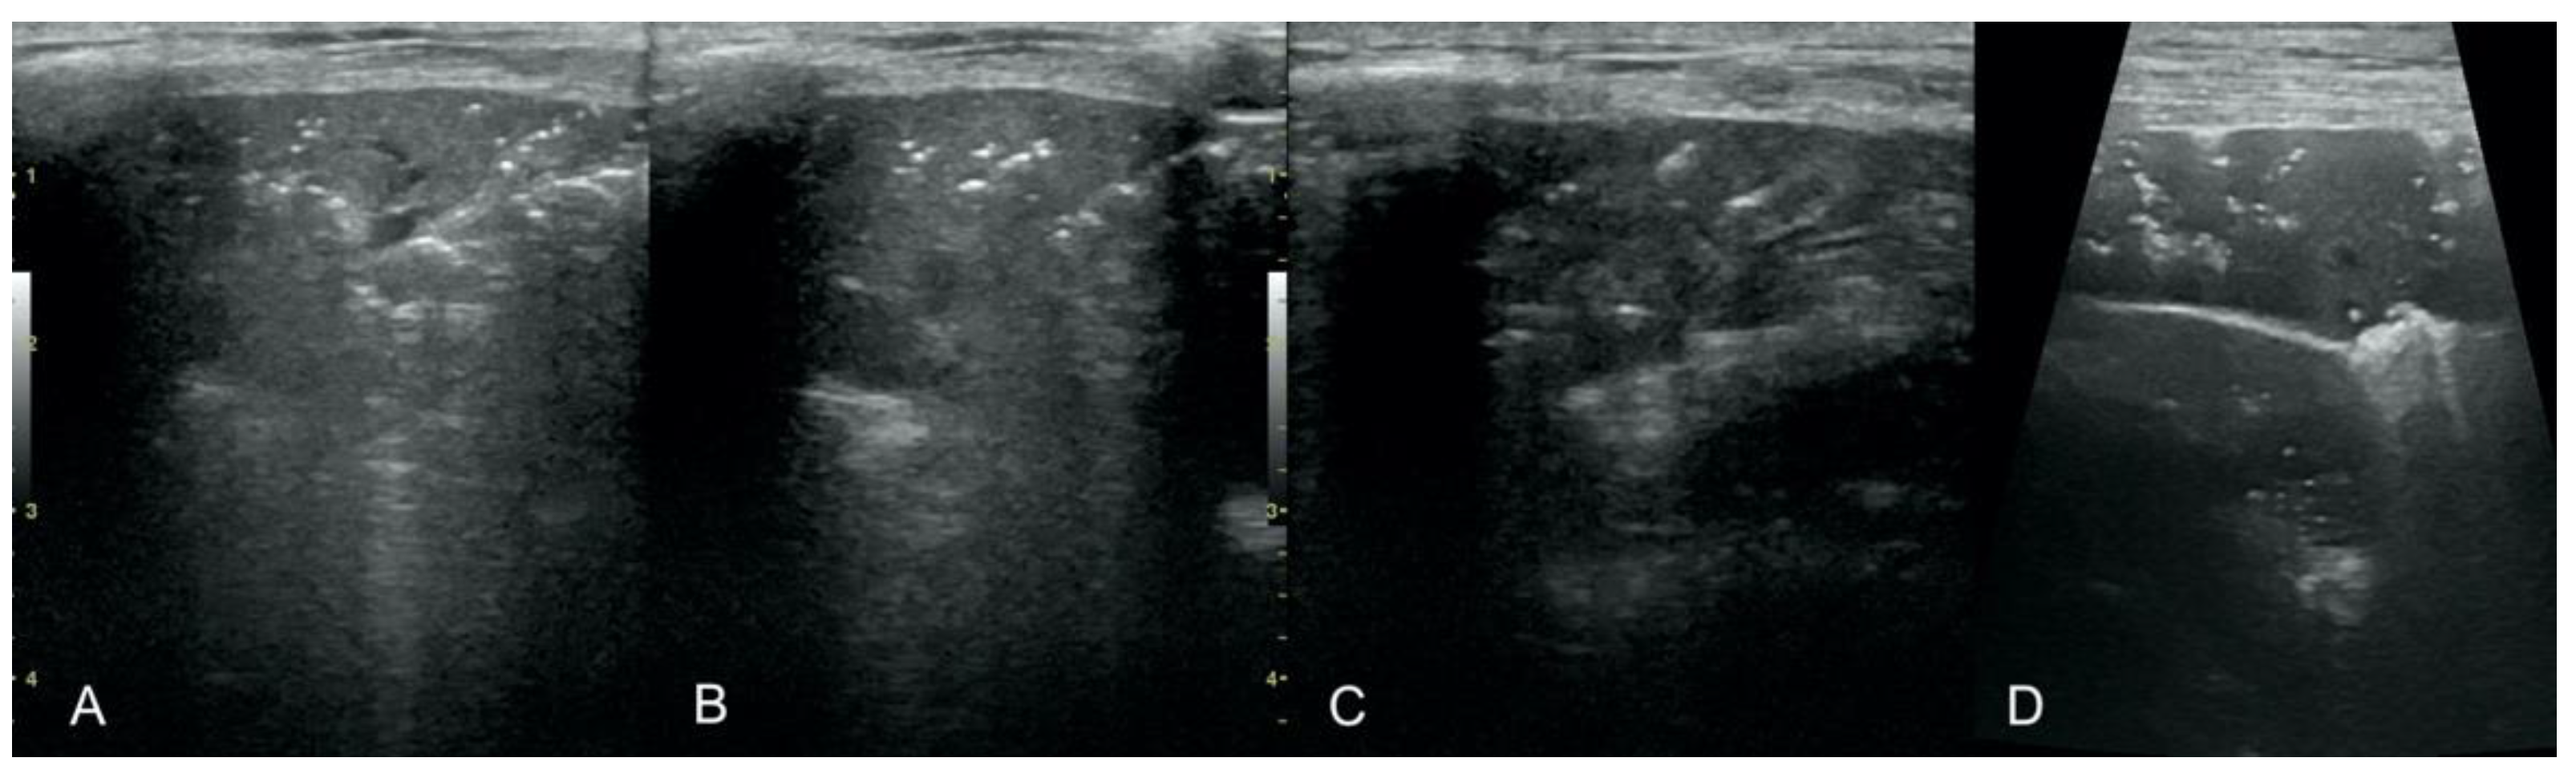

• Irregular and thickened pleural line, henceforth referred to as pleural thickening (Figure 1);

Figure 1. Irregular and thickened pleural line.

Figure 7. Hepatization with aeration in the course of pneumonia (AC) and lung cancer (D).